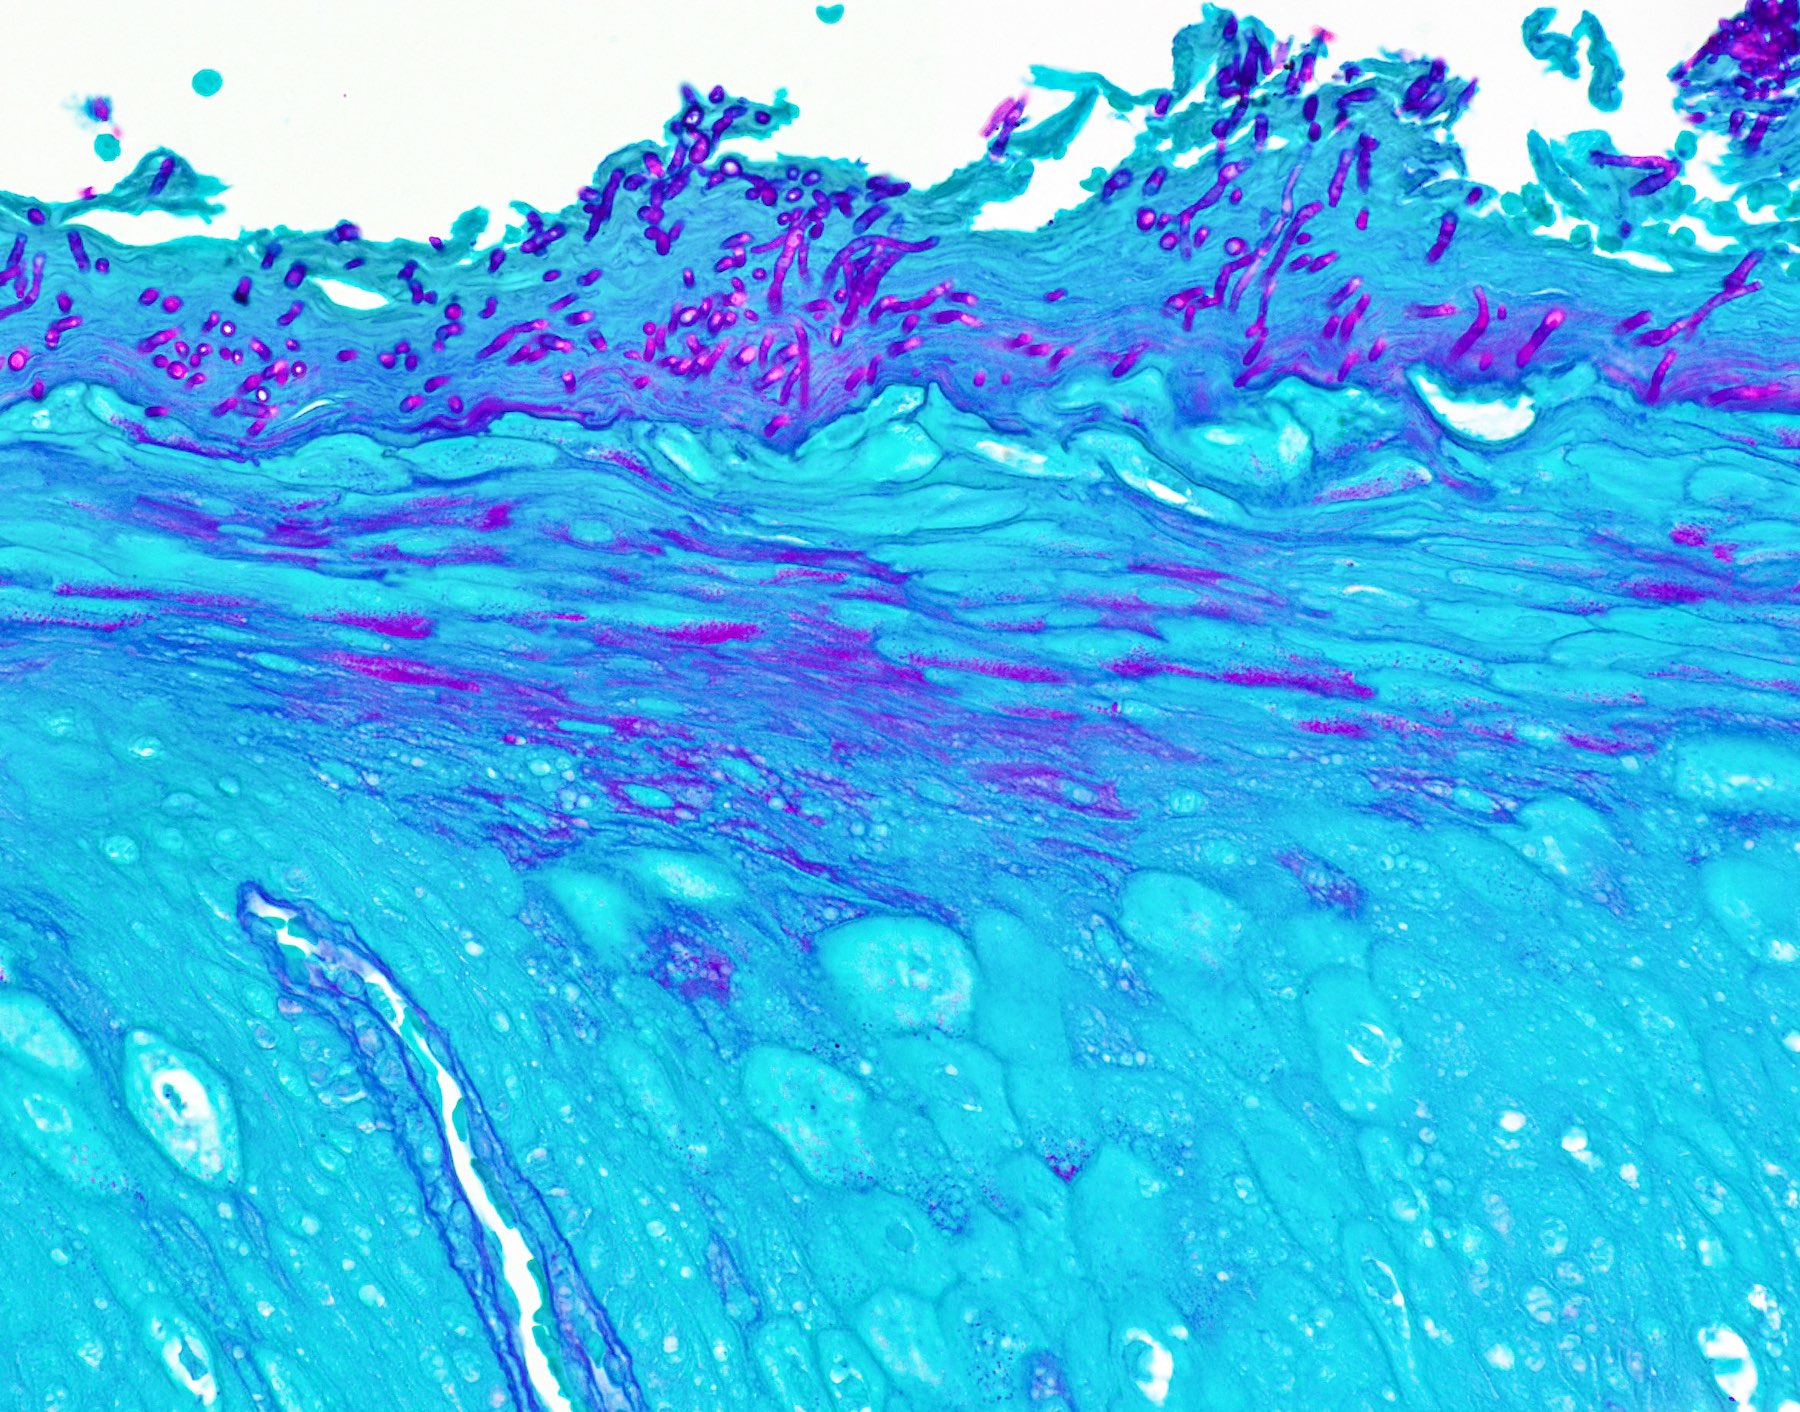

PEH in median rhomboid glossitis

The above biopsy was taken from the posterior dorsal tongue at the midline. What is the microscopic pattern of the epithelium called?

1. Pseudoepitheliomatous hyperplasia

A. Pseudoepitheliomatous hyperplasia. When combined with the clinical information / photograph, the overall diagnosis of this case is median rhomboid glossitis, which is a particular diagnosis made in a patient with a red patch on the middle portion of the posterior dorsal tongue. The epithelium often shows elongated, bulbous shaped rete ridges (pseudoepitheliomatous hyperplasia) and superficial candidal colonization, as highlighted here by a PAS stain. Answer B is incorrect because the epithelium does not show significant atypia or detached islands of invasive epithelium. Answer C is incorrect because there are no salivary ducts pictured above; however, squamous ductal metaplasia may be seen in association with pseudoepitheliomatous hyperplasia in a setting of necrotizing sialometaplasia, a condition most often diagnosed on the hard palate. Answer D is incorrect because although the epithelium is bulbous and hyperplasic, a prominent verrucoid surface architecture and keratin clefting are not identified.